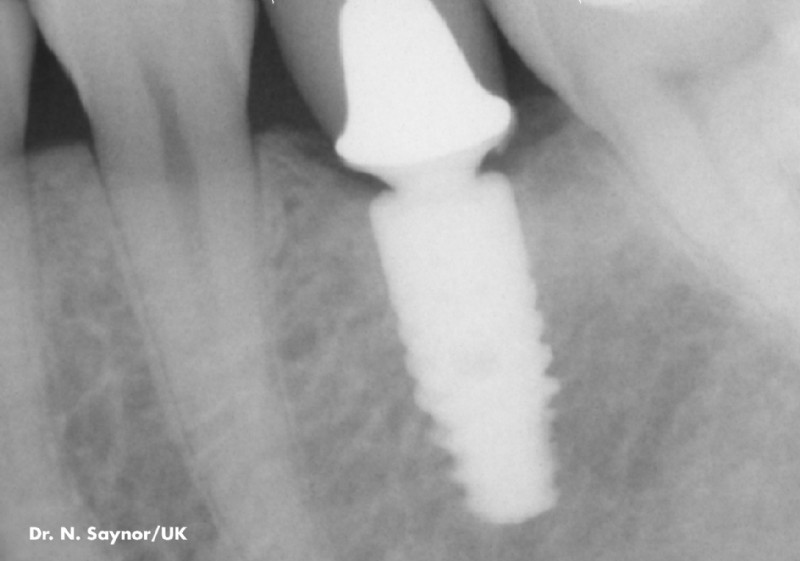

Hochqualitative künstliche Zahnwurzeln können natürliche Zähne sehr effektiv ersetzen. In einem ersten Schritt wird das Implantat-Bett aufbereitet, sodass das Implantat – eine Schraube aus Reintitan – problemlos in den Kiefer geschraubt werden kann. So können einzelne Zähne ersetzt oder Prothesen fixiert werden.